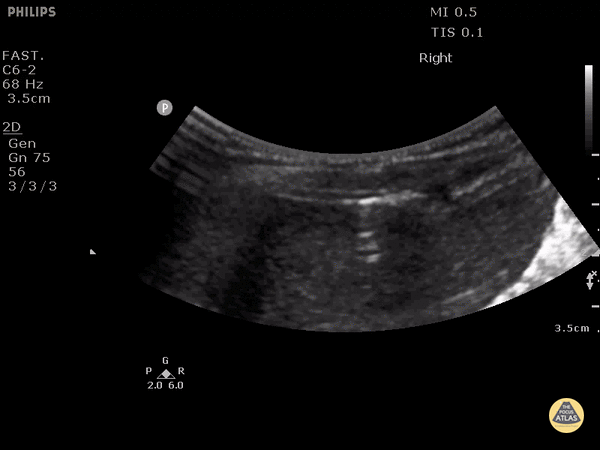

8 year old boy after pushbike handles went into abdomen. Erect CXR suggested small pneumoperitoneum. Initial POCUS in supine position showed normal RUQ, however this clip in left lateral position shows a small 'bubble' of air between liver and abdominal wall. Dr. Justin Bowra